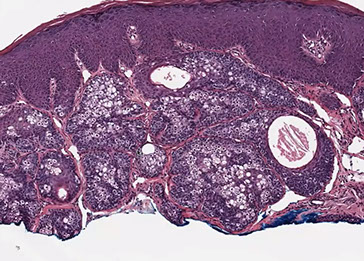

Pilomatrixoma

Trichohyaline granule (which are usually seen in hair shafts) in a pilomatrixoma

- aka calcifying epithelioma of Malherbe

solitary, bluish, firm (often calcifies), benign subepidermal spherical nodule

b9 hair follicle tumor

MC on face of kids or young adults

- 75% of childhood adnexal tumors

- can have multiple lesions in myotonic dystrophy

Sharply circumscribed cyst-like structure in dermis, possibly contiguous with hair follicle (may arise from hair matrix)

- can have inc mits (the malignant form is rare and usually very atypical)

- may have trichohyaline granules (which are usually seen in hair shafts)

3 cell types in fragmented cyst wall:

1) outer layer of blue (basophilic) basaloid martical cells with round nuclei and scant cytoplasm which dies and become dead keratin, which are the ghost cells

- imitate the cells in the root, or bulb of a normal hair follicle

2) mixed zone of eosinophilic cells c large round vesiculated nuclei

3) central zone sheets of keratinized pink "ghost" or "shadow" cells c distinct cell borders and central unstained nuclei

- difference from BCC: basaloid cells undergo abrupt keratinization and form "ghost" cells

Has foci of foreign body reaction, calcifications and ossification in shadow cell lobules

See melanin in shadow cells

Fibrotic stroma infiltrated with granulomatous inflam

Solid nests of basaloid cells may cause misdiagnosis of BCC

Ddx: Basal cell carcinoma c matrical differentiation (differs by continuity with epidermis and abrupt transition into shadow cells without the eosinophilic zone)